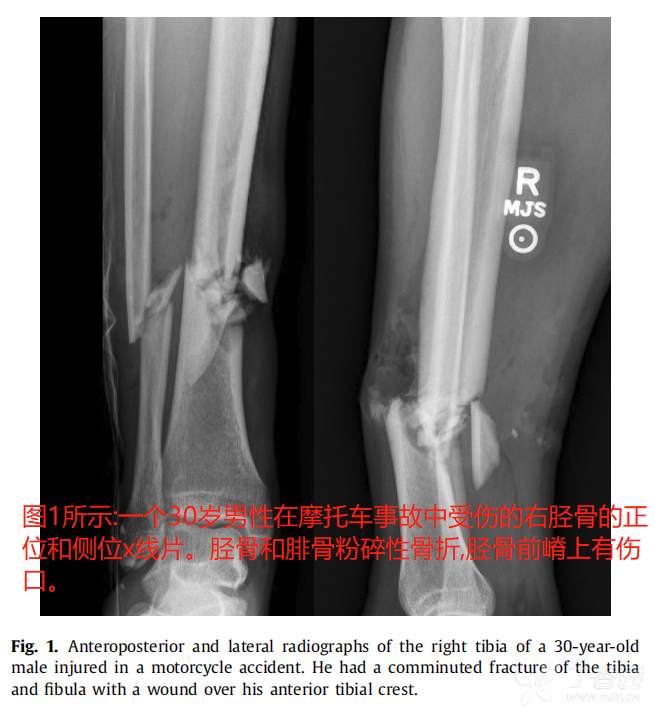

典型病例: